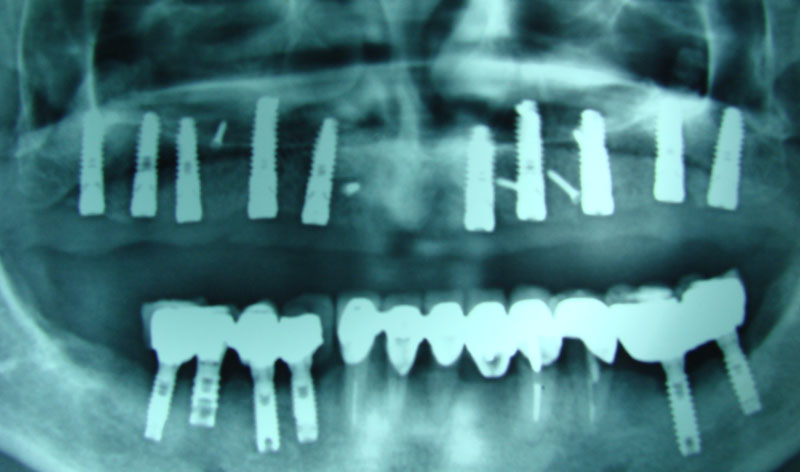

Existen muchas situaciones donde la pérdida y la atrofia ósea son tan graves que nos obligan a recurrir a la cresta iliaca del paciente, para conseguir el volumen óseo necesario para la correcta reconstrucción del maxilar. Así, la colocación de implantes será posible a los 3 meses.